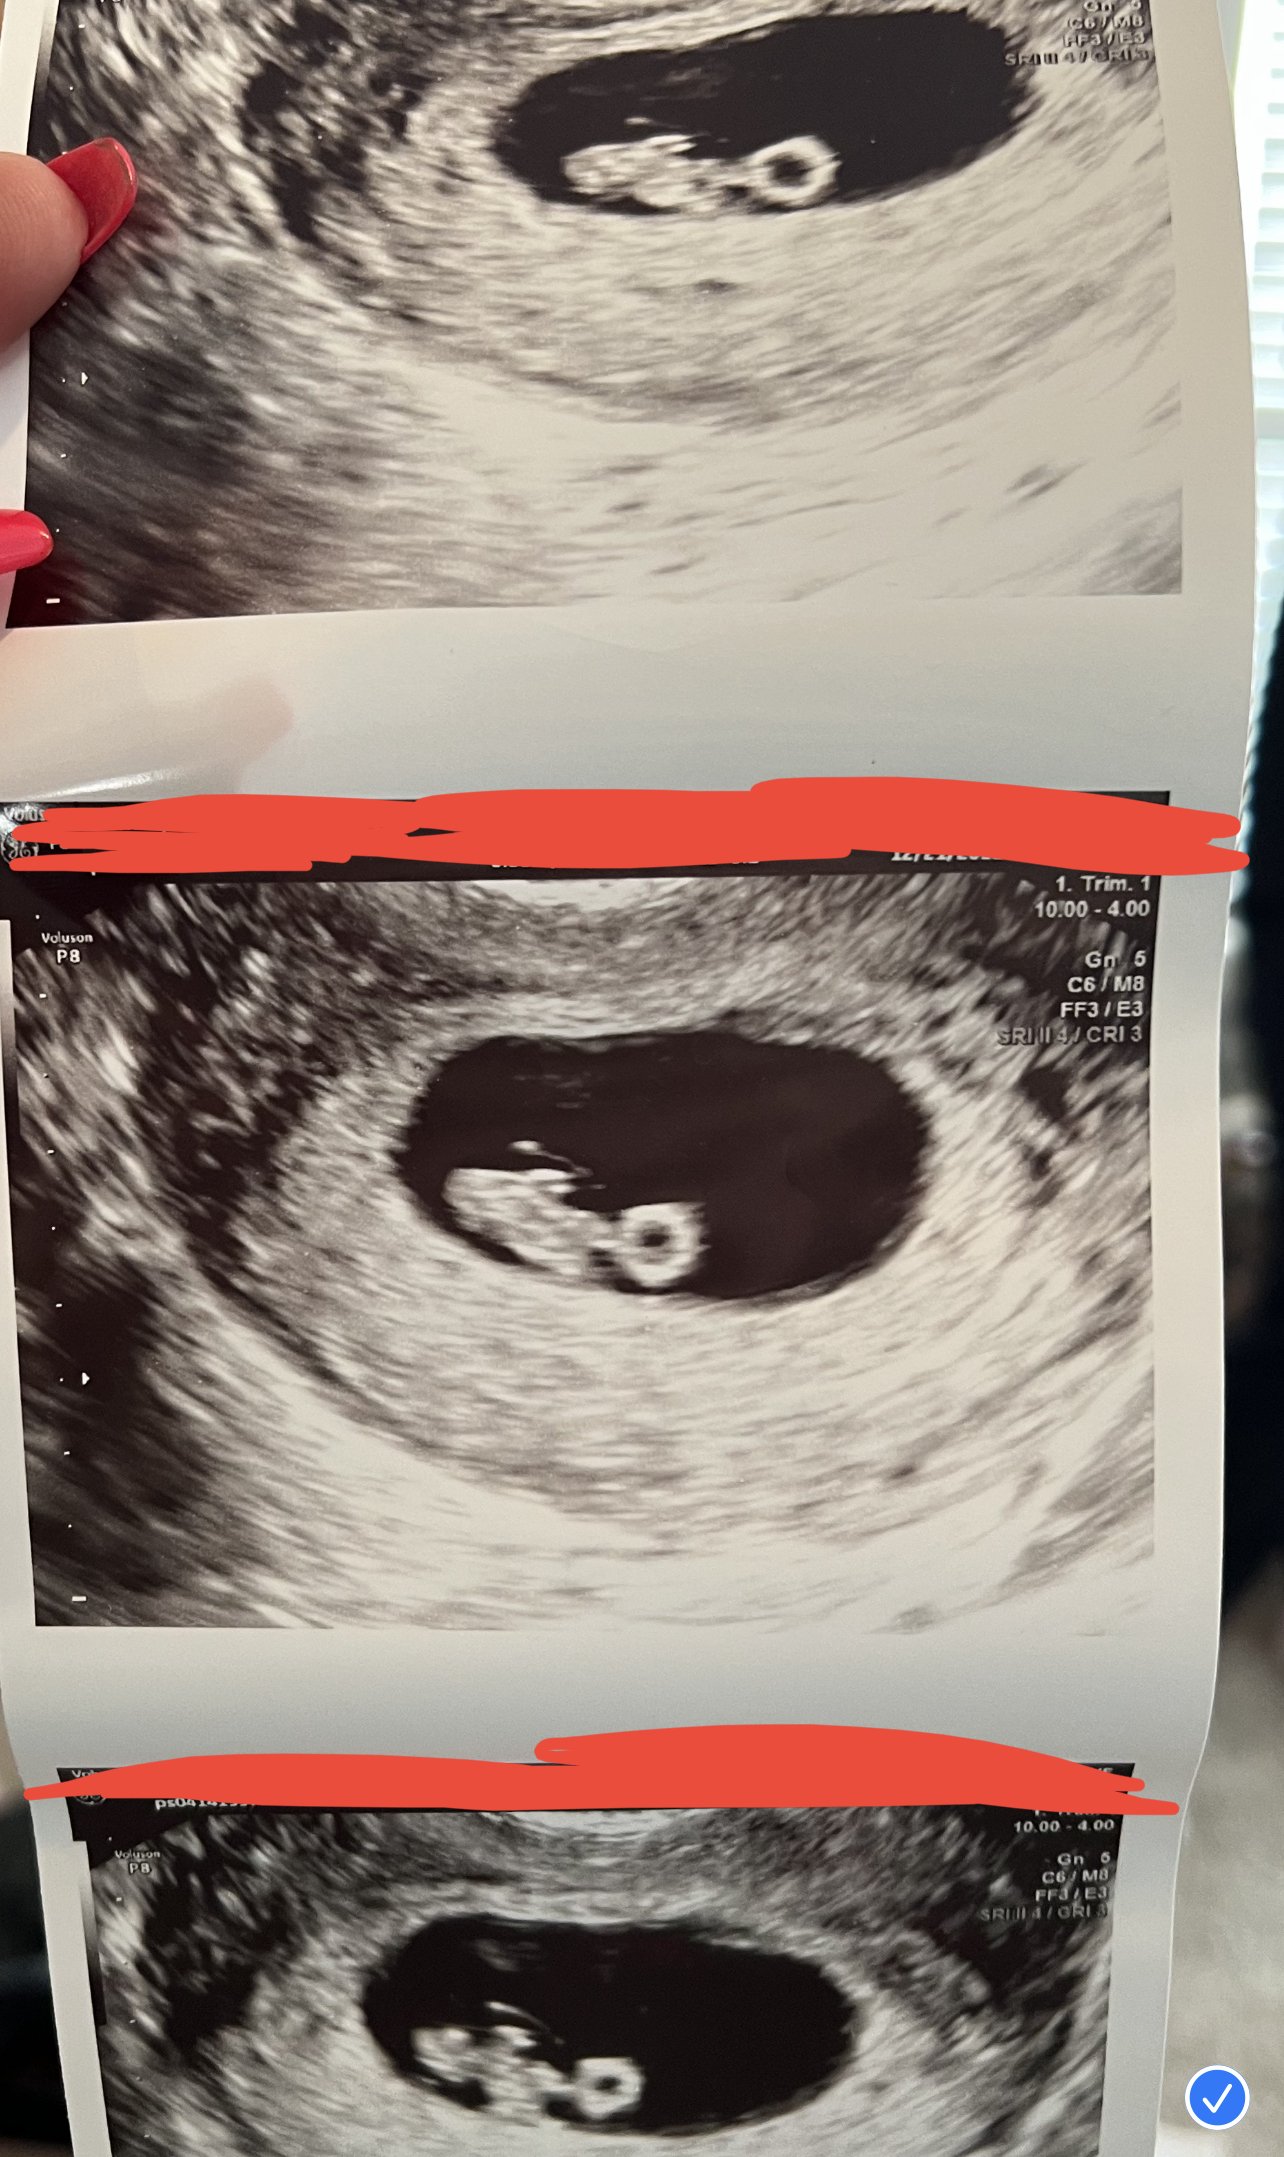

Just wanted to share two different ultrasound results in case it helps any of you. The doctor we saw for the first ultrasound came in right after and basically said we had a "slow" heartrate and could expect miscarriage. My research and instincts told me that was incorrect, and I pushed back. I had a blighted ovum last year, which was basically an empty sac at the same time (6 wks, 2 days) so seeing fetal pole and heartbeat seemed great to me! I was honestly shocked at the doctor's reaction.

The second doctor (we saw her today after the second ultrasound) told me it was irresponsible for them to flag anything over 100 at 6 weeks and that my first measurements were fine. It goes to show that there is variation among medical professionals, as well as different approaches, and on the earlier side, assuming certain elements are in place, it's ok to be optimistic!

SECOND ULTRASOUND Ultrasound date: 1/5/23 Gestational Age: 9 wks, 2 days Elements Present: Yolk sac, fetal pole, heartbeat CRL (crown rump length): 2.5cm Heart rate = 167 (per doctor, range should be 150-170) Due date = 8/8/23

For reference here are the previous ultrasound notes / measurements: Ultrasound date: 12/19/22 Gestational Age: 6 wks, 3 days Elements Present: Yolk sac, fetal pole, heartbeat CRL (crown rump length): .67 cm Heart Rate = 107 Due date = 8/10/23